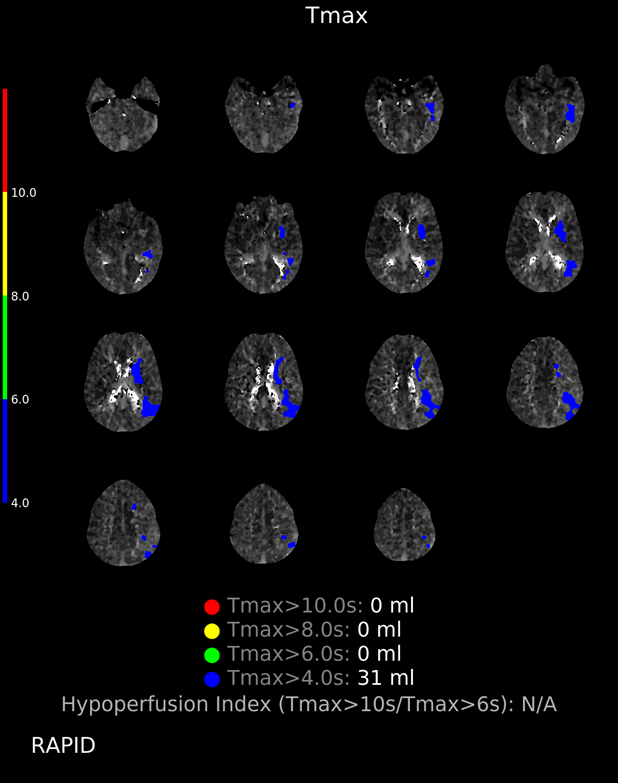

9/ CTA/P completed as well. LM1 thrombus now appears <occlusive (note that calcification makes vessel appear >open than it actually is), CTP without clear penumbra, but TMax high in posterior MCA division.

๐Ÿ‘‰ Recurrent events with no EEG correlate and with prolonged TMax make us think it was perfusional